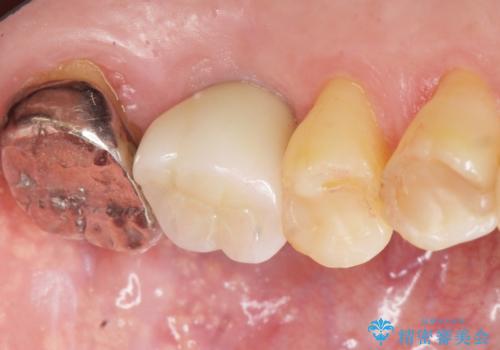

奥歯のインプラント ソケットリフト 60代男性

- 奥歯のインプラントをご希望し、来院された患者様です。

精査したところ上顎骨の厚みが薄かったため、ソケットリフト(上顎洞底挙上術)を併用してインプラント治療を行いました。

審美的・機能的な仕上がりに喜んで下さいました。

また、半年という比較的短期間でインプラント治療が終わったことにもご満足頂けました。

インプラントの種類:スプライン ツイスト (保証期間:5年)

クラウンの種類:ベレッツァクラウン (オールセラミック)

固定様式:セメント固定